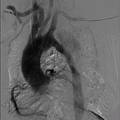

- 本项目利用数字化三维重建技术,通过对临床患者胸腔原始CT或MRI扫描数据进行个性化三维图像重建,实现人体胸主动脉夹层动脉瘤诊断的数字化三维可视。进一步地,运用血流动力学的基本原理和数学有限元模型,进行三维血流动力学的计算机数值模拟,获取了在一个心动周期内,胸主动脉内的血液流场、壁面压力和截面速度分布等数据,并在此基础上分析研究血流压强、速度与心血管疾病形成之间的联系。

- 本项目采用结合数学、医学、工程学的跨学科交叉研究方式。首先通过对临床采集到的患者胸腔原始CT或MRI扫描数据利用图像处理软件进行个性化三维图像重建,分离并重构了胸主动脉内腔真实的三维模型,得到患者病变胸主动脉的三维立体图像。通过3D模型的建立,可以方便地从任意视角观察胸主动脉病变情况,由此可更加全面、清晰地了解病变的整体及细节,实现人体胸主动脉夹层动脉瘤诊断的数字化三维可视。 进一步地,运用血流动力学的基本原理和数学有限元模型,进行三维血流动力学的计算机数值模拟,获取了在一个心动周期内,胸主动脉内的血液流场、壁面压力和截面速度分布等数据,并在此基础上分析研究血流压强、速度与心血管疾病形成之间的联系。 本项目希望通过基于血流动力学的辅助诊疗技术模拟人体心血管系统的真实血流情况,利用计算机数值模拟获得的数据,在为临床诊断提供有效定量分析依据的同时,根据患者的病情状况,在一定程度上,揭示并初步预测心血管疾病发生和发展的过程,使医生在对患有血管疾病的患者进行临床诊断及治疗时获得病人患病位置处血流的实时三维影像及血流速度与压力等数值,进而辅助医生使其对患者的病情予以的准确诊断和正确治疗,从而提高现有的临床诊治的水平。

- 心血管疾病对人体健康有巨大威胁,近年来因心血管疾病导致死亡的病例呈不断上升趋势。数据显示,目前,每15秒就有一位中国人被心脑血管疾病夺去生命。 目前心血管疾病主要的临床诊疗手段是通过CT、MRI数据直接进行图像重建,但只局限于三维图像,不能分析患者患病部位的血流特征。而我们基于血流动力学的研究恰恰能弥补这一空白。 首先,通过临床上采集到人胸CT扫描数据运用专业图像处理软件分离并重建人体胸主动脉弓的三维仿真模型。其次,运用计算流体力学的基本原理和血流动力学的相关知识对人体胸主动脉中的脉冲血流进行三维数值模拟和研究,计算出人体胸主动脉内血液流动在心动周期内不同时刻的血液流场、壁面压力、速度分布。最后通过验证血流速度和压力变化剧烈区域与临床主动脉夹层易发区域相吻合,说明血流速度和压力对胸主动脉夹层病例的发生和发展有影响。 通过以上基于血流动力学的有限元分析验证胸主动脉夹层病例易发区域的研究,将这一研究方法运用于临床,可使得医生在对患有血管疾病的患者进行临床诊断及治疗时获得病人患病位置处血流的实时三维影像及血流与压力等数值,进而辅助医生使其对患者的病情予以的准确诊断和正确治疗。